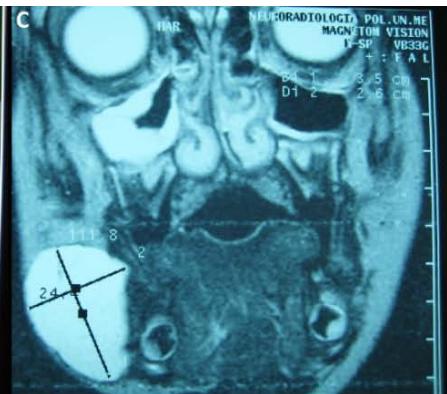

Figure/Patient 2

A case of right mandibular lymphangioma in a 10 year-old boy, hypoechoic with some septations and no blood vessels (A) and hyper-intense on T2 axial (B) and coronal (C) MR scans.